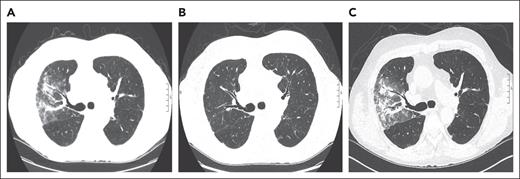

A 70-year-old man with a history of myelofibrosis received a myeloablative allogeneic PBSCT. Three years after HCT, he developed liver cGVHD that was treated with prednisone (80 mg/d or 1 mg/kg per day) and mycophenolate mofetil (1 g twice daily). His liver cGVHD stabilized, and prednisone was tapered to 8 mg/d and mycophenolate mofetil was discontinued over the course of 8 months. Two months later, he started experiencing fever and cough. A CT scan of the chest showed diffuse ground-glass opacities with nodules in the right upper lobe (Figure 3A). Infectious workup, including BAL, was unrevealing, and a diagnosis of HCT-OP was established. His respiratory symptoms and radiographic abnormalities resolved after his prednisone was escalated back to 1 mg/kg and mycophenolate mofetil was reinitiated as a corticosteroid-sparing agent (Figure 3B).

Representative serial axial images of a noncontrast CT scan of the chest for case 2. (A) Axial CT image, showing peribronchovascular consolidations and ground-glass opacities in the right upper lobe. (B) Image showing a complete resolution of radiographic abnormalities after escalating prednisone to 1 mg/kg per day and reinitiation of mycophenolate mofetil. (C) Image showing reappearance of ground-glass opacities with peribronchovascular consolidations in the right upper lobe when the prednisone was tapered to 10 mg/d and positive cytomegalovirus PCR in BAL. Notably, lung findings appear similar to panel A, when his HCT-OP was initially diagnosed.

The patient remained stable until prednisone was tapered to 10 mg over a period of 4 months, at which point he again developed fever and cough. A CT scan of the chest showed patchy consolidation and ground glass in the right upper lobe, with similar geographic distribution to his previous HCT-OP (Figure 3C). BAL was performed, which was positive for cytomegalovirus (CMV) by PCR, but serum CMV PCR was negative. Lung biopsy was not pursued for a definitive diagnosis of CMV pneumonia given the procedural risk. After a multidisciplinary discussion, ganciclovir was started, and the patient’s symptoms improved while his prednisone remained at 10 mg. Follow-up CT scan of the chest also showed resolution of right upper lobe abnormalities (image not shown).

Interestingly, we have not observed migratory pulmonary infiltrates, which are often described as a feature of COP.1,52,53 Instead, as shown in this case, recurrence occurs in a radiographic distribution akin to the index episode (Figure 3A,C). We have observed this to be the case even when the recurrence of HCT-OP is separated by years from the index occurrence. The exact mechanism is unknown but perhaps is similar to recall radiation pneumonitis.